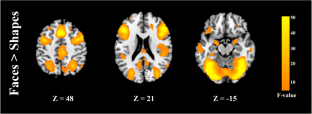

Numerous functional magnetic resonance imaging studies have been conducted to elucidate emotion processing of patients with bipolar disorder (BD), but due to different inclusion criteria used, especially for the history of medication use, the results for euthymic BD patients are inconsistent. For this reason, brain functional effects of psychopharmacological treatments on BD patients have been investigated by numerous fMRI studies, but there is no existing report for brain functional effects of different mood stabilizers. In this study, we compared the emotion processing in BD patients treated by two popularly used mood stabilizer, lithium (N = 13; 30 ± 9 years) and valproate (N = 16; 33 ± 8 years), as well as healthy controls (HC; N = 16; 29 ± 7 years). Two emotional tasks were applied in this study: one used emotional pictures of everyday objects and scenes, and another used emotional facial expression pictures. The main findings were that BD on lithium showed increased fMRI activation in the right dorsal anterior cingulate cortex and bilateral lingual gyrus in response to the positive pictures relative to neutral pictures compared with BD on valproate and HC. Besides, no abnormal activation was observed in the amygdala. Limitations of this study comprise the small sample size and the cross-sectional design. Therefore, the results were suggestive of a different effect of lithium and valproate on brain activities during emotion processing but no causal role can be proposed. The enduring impairments in euthymic state could provide clues to the brain regions involved in the primary pathology of BD.

Fig. 2